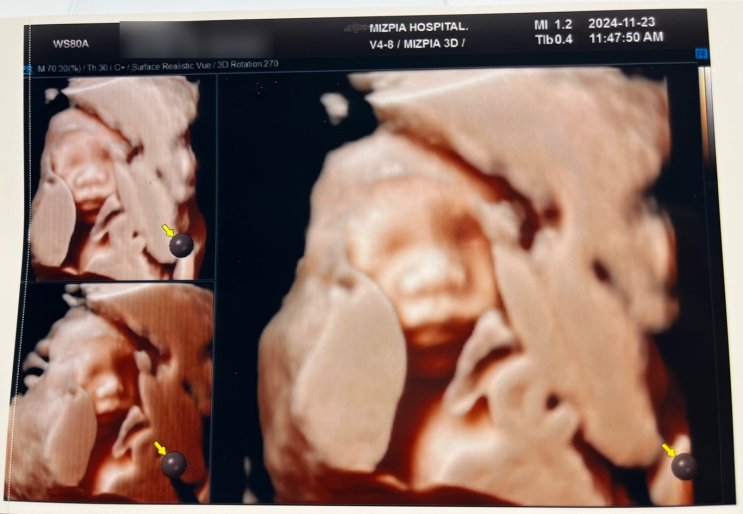

[임신일기] 산모들이 두려워하는 임당검사 (24주4일)

주변에서나 어플에서나 많이 듣고 봐왔던 임당검사가 나에게도 다가왔다. 임당검사 전까지는 한방이 보고 ...

[임신일기] 떨리는 21주차 정밀초음파 검사 (21주 2~3일)

1,2차 기형아 검사에서 한번의 이벤트가 있어서 정밀초음파 하는 날이 너무 떨렸다. 제발 무사히 넘어가길 ...